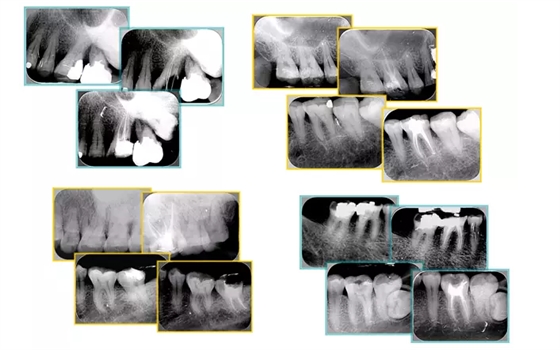

右圖及下圖為器械折斷的 X 線片。箭頭處示折斷器械。

解決方法: ( 1 )取出。 ( 2 )通過。 ( 3 )重新確定工作長(zhǎng)度,充填。 ( 4 )根尖手術(shù)。

器械折斷可以不用取出,取出的原因多是患者心理因素。留在里面的器械關(guān)鍵是進(jìn)行消毒,預(yù)防性使用抗感染藥物,預(yù)防感染。

右圖箭頭處示臺(tái)階形成。

解決方法: ( 1 )器械預(yù)彎。 ( 2 )若出現(xiàn)銼的螺紋擰緊,立即換用小號(hào)銼。 ( 3 )一旦到達(dá)WL,即按照從小到大順序預(yù)備根管。 ( 4 ) H銼幫助提高切割效率。